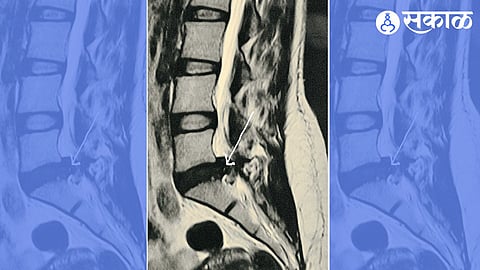

आपल्याला माहीतच आहे, की कंबरेच्या ​दोन मणक्यांमधल्या चकत्या काही वेळा घसरतात. स्लीप्ड डिस्क किंवा घसरलेली गादी या नावानंही लोकांना याबद्दल माहिती आहे. काही वेळा त्या घसरलेल्या चकतीचा तुकडा शेजारच्या एखाद्या नसेत घुसतो किंवा दाब देऊ लागतो.

सायटिकाच्या वेदना सुरू होऊ शकतात. या वेदनांतून मुक्ती मिळवायची, तर काही वेळा शस्त्रक्रियेला पर्याय नसतो. आज या शस्त्रक्रिया अत्याधुनिक उपकरणांनी केल्या जातात. शस्त्रक्रिया झाल्यानंतर त्या ठिकाणी टाकासुद्धा घ्यावा लागत नाही.